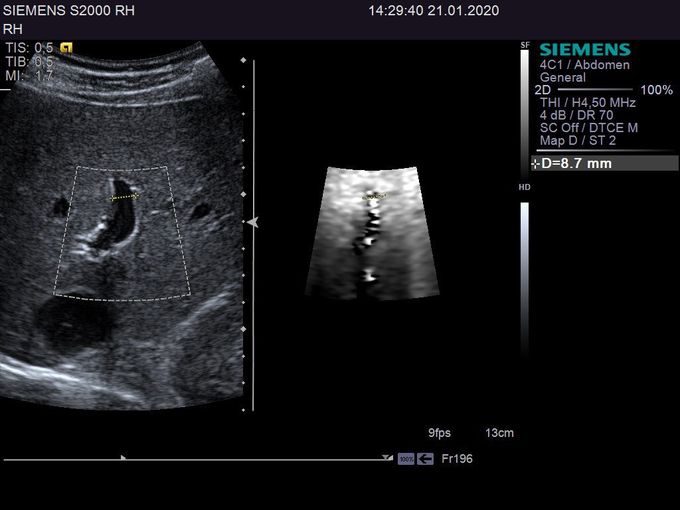

Кроме новой техники, можно заказать восстановленные медицинские системы: ультразвуковые сканеры, томографы, флюороскопы, ангиографы и хирургические установки С-дуга.